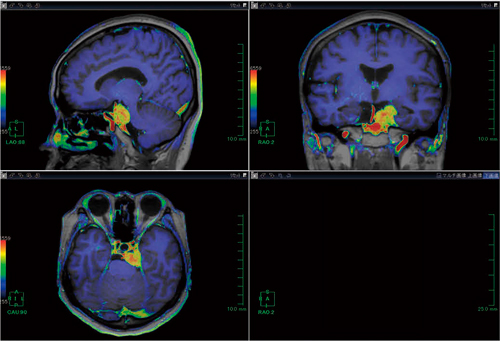

脳腫瘍や脳卒中などの虚血性疾患においてASLの有用性は高いが,位置関係の把握が困難な場合も見受けられる。そこでASLデータ中のperfusion imageデータとT2強調画像をfusionさせることにより,位置関係をより正確に描出することが可能である(図1〜4)。

図1 頭部MRI 3D T1強調画像とperfusion imageのfusion画像:三叉神経鞘腫症例

図3 頭部MRI T2強調画像とperfusion imageのfusion画像:脳梗塞症例 |